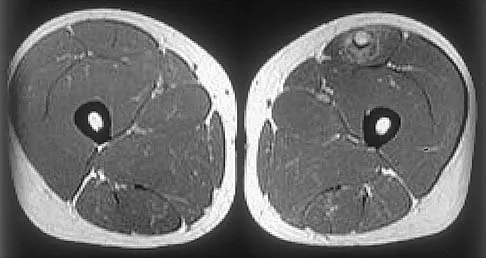

Figures 24a through 24c show the coronal T1-weighted, T2-weighted fat-saturated, and T1-weighted fat-saturated gadolinium MRI scans of the proximal thigh of a 52-year-old woman who reports a mass in the medial thigh and groin area. She notes that the fullness has grown in size over the course of many months. Based on these findings, what is the most likely diagnosis?